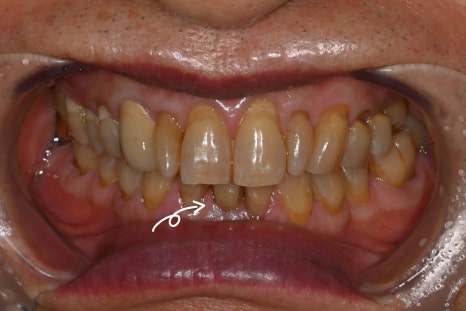

60대 남성 환자분의 아래 앞니 임플란트 수술 사례를 소개합니다.

기능과 심미성을 동시에 회복하는 맞춤 치료가 필요했습니다.

수술 3개월 후 최종보철물까지 장착한 사진

수술 후 3개월 뒤 최종 보철물까지 장착하여

모든 진료가 마무리 되었습니다.